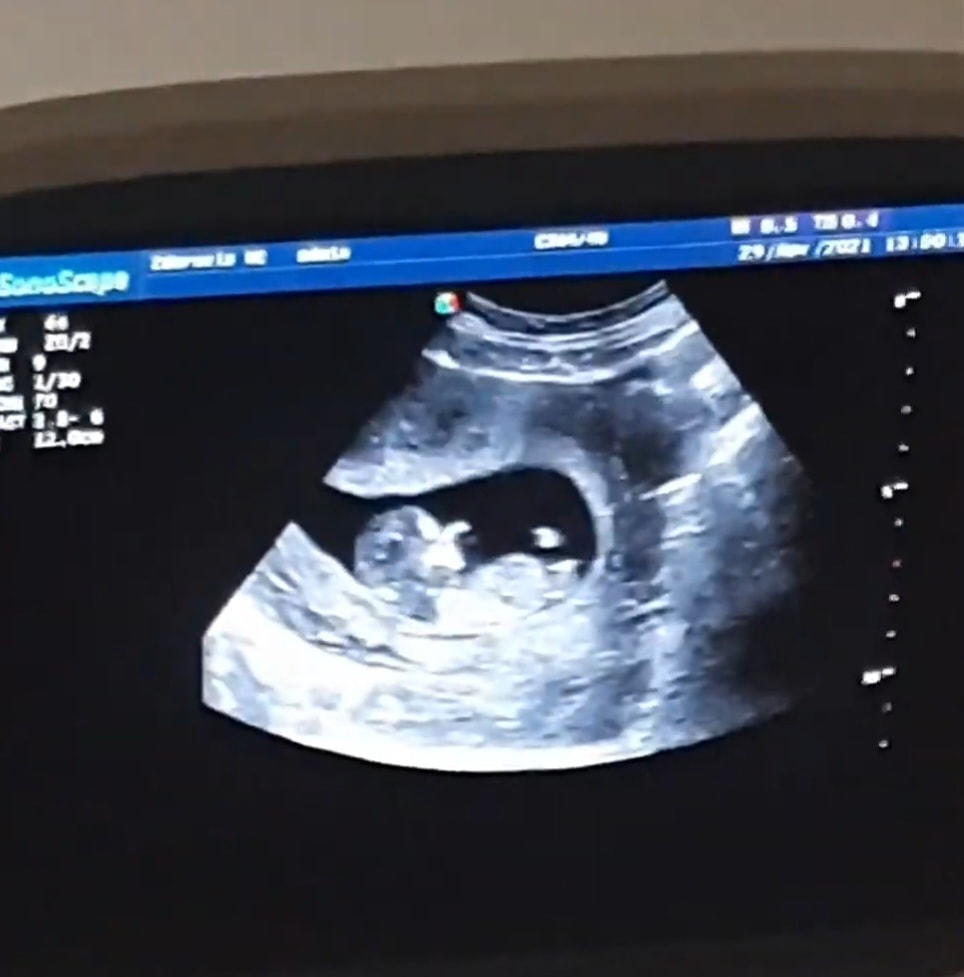

Мальчик или девочка?

Пол малышаСегодня был первый скрининг, знаю что пока рано говорить о том какой пол, но всё же интересно.

Кого вы видете?)

Мама тройняшек, врач так же сказала, что девочка, но лучше мол узнавать пол в 14-16 недель, т.к сейчас может быть результат неточный.Спасибо за ответ!😊

Vasilisa, девочка 90%) поверьте моему опыту, мальчики в 12 недель выглядят абсолютно по другому 😉😀

Думаю, что скорее мальчик)

Похоже на снимок моего младшего)